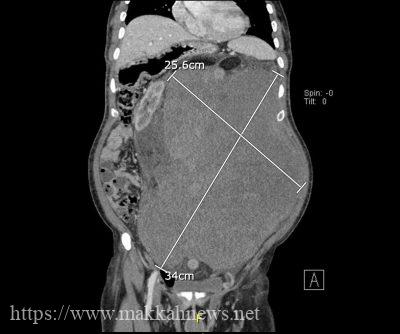

انهك ورم ضخم بوزن ١٨ كجم مريض بالعقد السادس من العمر ملأ تجويف البطن وحرمه الاكل واقعده عن الحركة، وبتدخل طبي تكاملي من فريق الجراحات التخصصية والاقسام المسانده بمدينة الملك عبدالله الطبية بالعاصمة المقدسة تم استئصال كامل الورم بنجاح في عملية كبيرة ومعقدهواستقبلت المدينة الطبية الحالة عبر برنامج احالتي محولة من مستشفى الملك فيصل بمكه وكان يعاني من ورم ضخم يملأ تجويف البطن بالكامل مسبباً ضغطاً على الأمعاء وعدم القدرة على الأكل ونقص بالوزن واعاقته عن الحركة. وتم اخضاع المريض لفحوصات كامله واشعات مقطعية ورنين مغناطيسي مع اخذ خزعه من الورم اظهرت نتائجها وجود ورم خبيث من نوع الساركومي الشحمي مع ضغط على الامعاء والقولون المستعرض الايسر ودفعهما الى الجهة اليمنى من البطن مسبباً عطباً للكلية اليسرى ودفعها الى الجانب الايمن وكذلك الوريد الاجوف السفلي